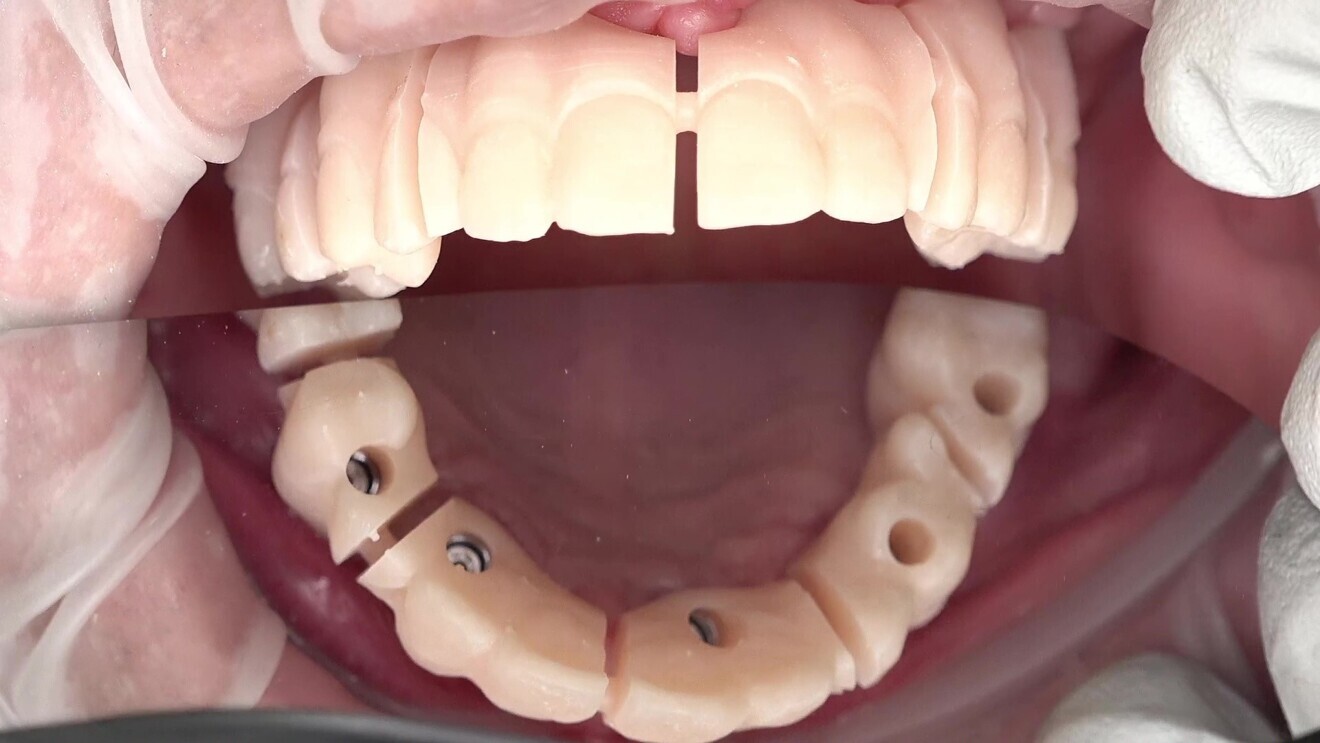

After the digitisation of the implants, two sets of 3D-printed try-ins were fabricated for both jaws. The first set, the validator set, was designed with gaps between the implant positions (Fig. 7). These gaps allowed for the detection of tension when the validator was seated, fractures occurring in the small gaps if tension was present. This step ensured that the final prostheses would fit accurately and comfortably without undue stress on the implants or surrounding tissue (Figs. 8–10). The validators had the same design as the second set of try-ins, the only difference being that the validators were cut between the implants using a virtual disc cutter and the attachment function in exocad software. It is crucial to ensure that the titanium bases or bar is firmly seated within the validator, which can preferably be achieved using resin cement. The validator should be retained with the same torque as the manufacturer recommends for the final restoration.

Fig. 7: 3D-printed validator try-in with gaps between implant positions.

Fig. 8: Seating of the validator try-in in the patient’s mouth.

Fig. 9: Validator try-in seated in the patient’s mouth.

Fig. 10: Adjusted validator try-in without fractures in the lower jaw.